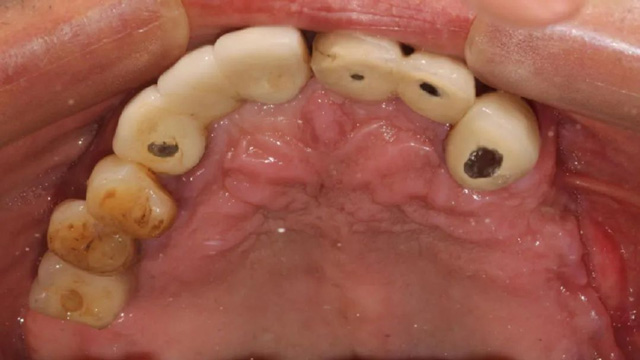

手术中拆除的种植体

“我们通过上半口即拔即种、即刻修复治疗,将他上面残留的种植体拆除,同时拔掉无法保留的牙齿,手术同期埋入6颗种植体,术后佩戴了临时牙冠。由于骨量不好,有3颗种植体采用倾斜植入,1颗做了上颌窦提升植入。”